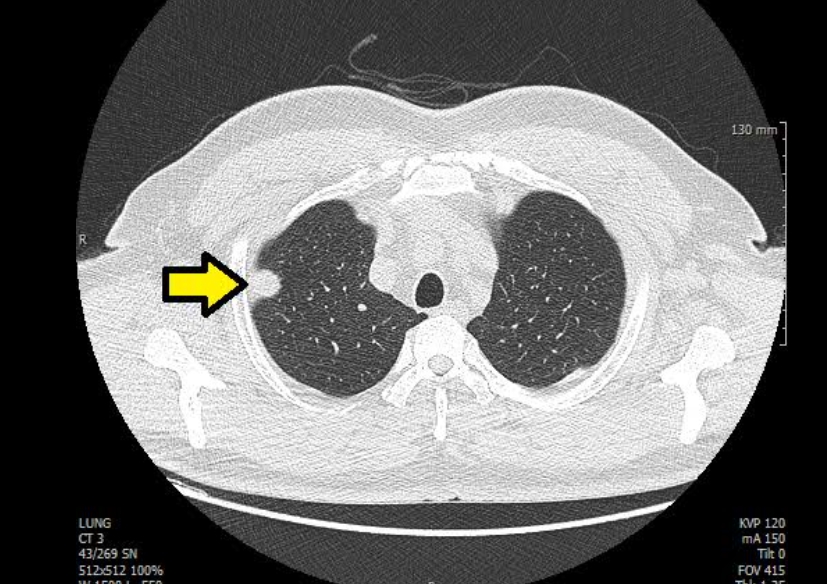

흉부ct로 볼수있는 질환 폐질환뿐 아니라 심장과 혈관, 흉막, 림프절, 뼈 구조까지 한 번에 보여줍니다. 폐렴, 결핵, 폐기종, 기관지확장증, 간질성 폐질환 같은 호흡기 질환은 기본이고, 폐에 생긴 작은 결절이나 혹도 세밀하게 확인할 수 있습니다. 폐암이나 전이암처럼 초기에 증상이 거의 없는 병은 CT로 발견되는 경우가 많아요.

흉부CT는 병이 있는지 없는지를 넘어서, 병의 진행 정도와 주변 장기 침범 여부까지 보여줍니다. 예를 들어 폐암의 경우, 5mm 미만의 아주 작은 결절까지 찾아내고, 종양이 혈관이나 기관지에 닿았는지도 확인합니다. 초기에 잡아내면 완치율이 크게 높아지죠.

또한 폐렴이 감염인지, 결핵성인지, 종양에 의한 것인지도 구분할 수 있습니다. 엑스레이에서는 그냥 ‘흐린 그림자’로만 보이던 것도, CT에서는 염증의 경계와 내부 구조까지 뚜렷하게 드러납니다.

A. 흉부ct로 볼수있는 질환 폐결절은 말 그대로 폐 안에 작은 혹이 있다는 뜻입니다. 대부분 양성(암이 아님)이고, 오래된 염증이나 석회화에 의한 것일 수도 있습니다. 그러나 결절의 크기가 8mm 이상이거나, 형태가 불규칙한 경우에는 추가 검사가 필요합니다. 영상의학과에서는 결절의 밀도, 경계, 주변 변화 등을 세밀하게 분석해 암 가능성을 판단합니다.